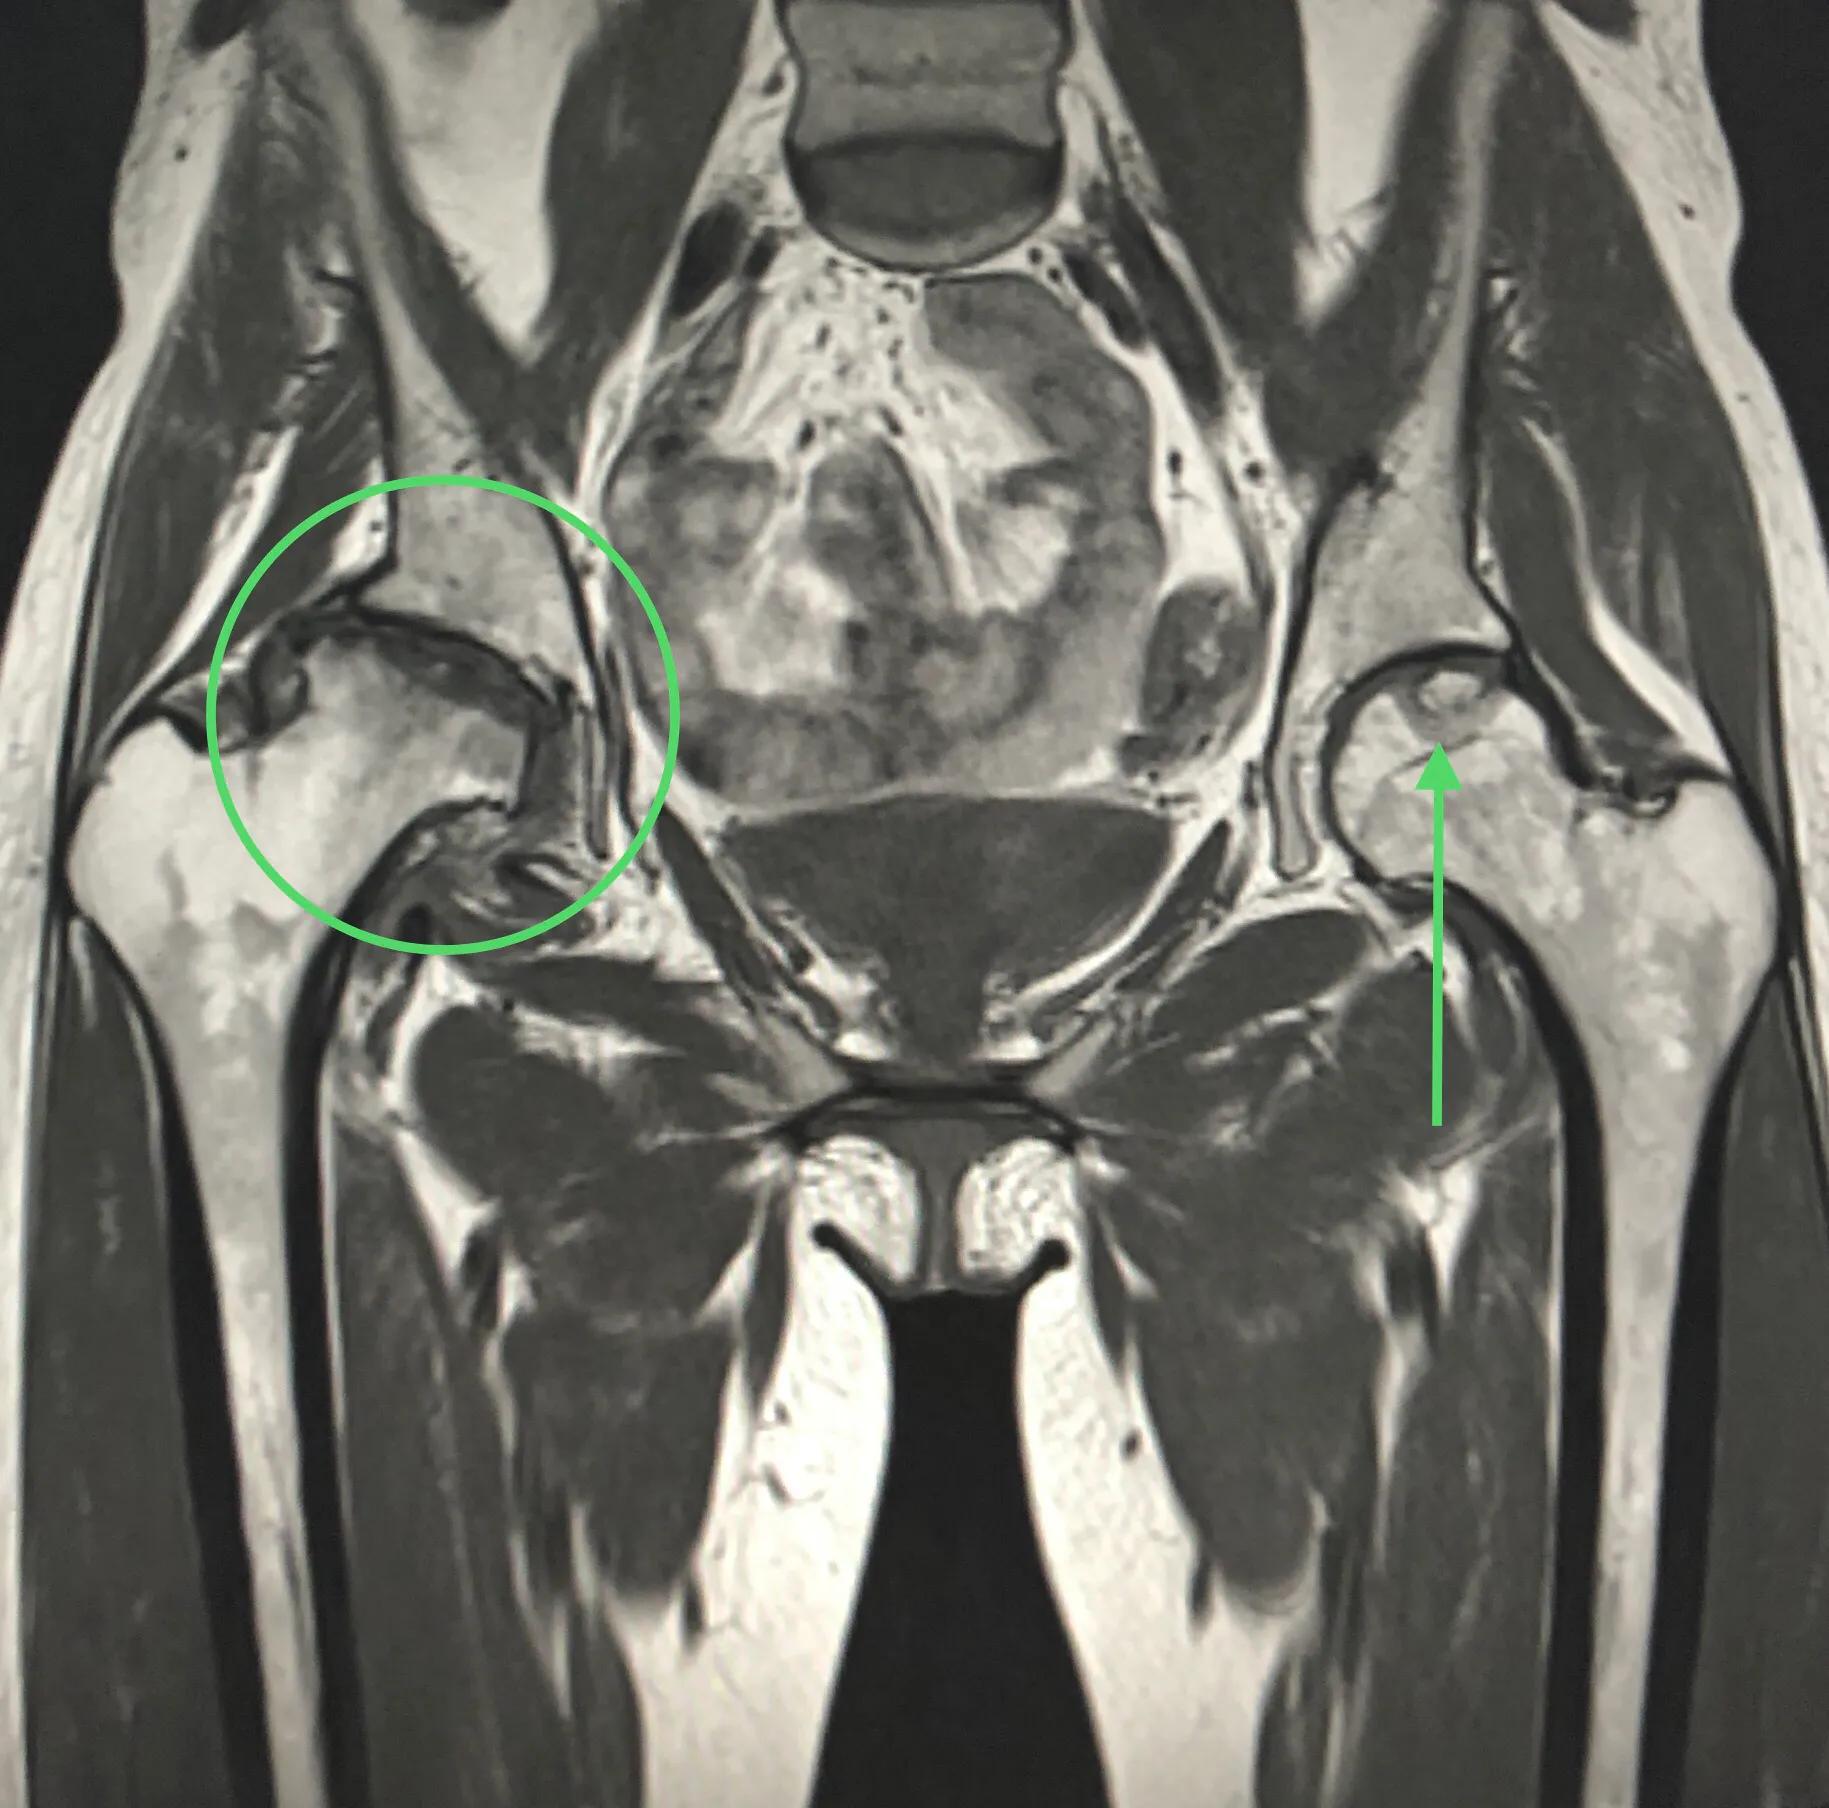

图6: MRI。右侧股骨头坏死4期,圆圈示。已完全失去股骨头形态。左侧股骨头坏死1期(很早期)。

图9MRI右侧股骨头坏死2期(箭头),对比左侧正常股骨头容易理解。